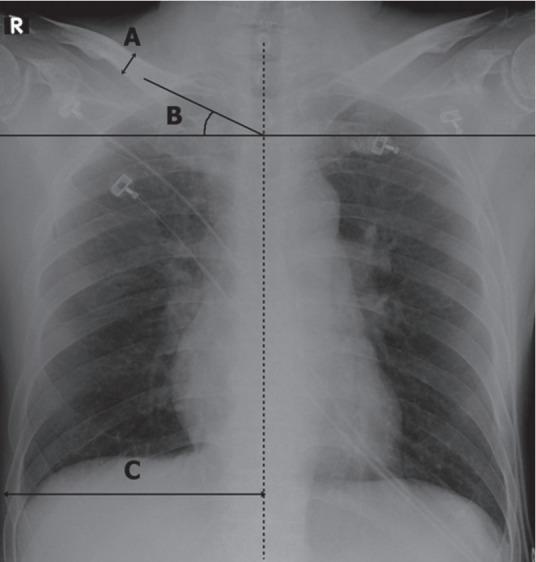

The aim of the present study was to investigate the relation between shoulder position and subclavian central venous (SCV) catheter misplacement. The shoulder position was estimated using clavicular tilt angle (CTA) values observed on anteroposterior chest X-ray images.

A retrospective case-control study was conducted on all adult patients who underwent SCV catheterization in the emergency department during a 12-month period. Collected data included patient age, sex, diagnosis, catheterization side, catheter misplacement, and physician's level of experience in catheterization. The CTA and other radiological variables such as the ipsilateral transverse length of the thorax and thickness of the clavicle were investigated.

Among all central venous catheterizations (n=1,599), the subclavian route was used 981 times (61.4%). There were 51 misplacements of SCV catheters (5.2%) during the study period. There were no differences in the sex, age, blood pressure, and diagnosis between the two groups. The CTA values were 28.5°±7.3° and 22.6°±6.3° in the misplacement group and control group, respectively (95% confidence interval, 3.6 to 8.1; P<0.001).

In this study, the CTA was found to be 5.9° larger in the misplacement group than in the control group. Assuming that CTA indicates the shoulder position, our findings suggest that the chance of SCV catheter misplacement may be reduced by avoiding the shoulder elevated.